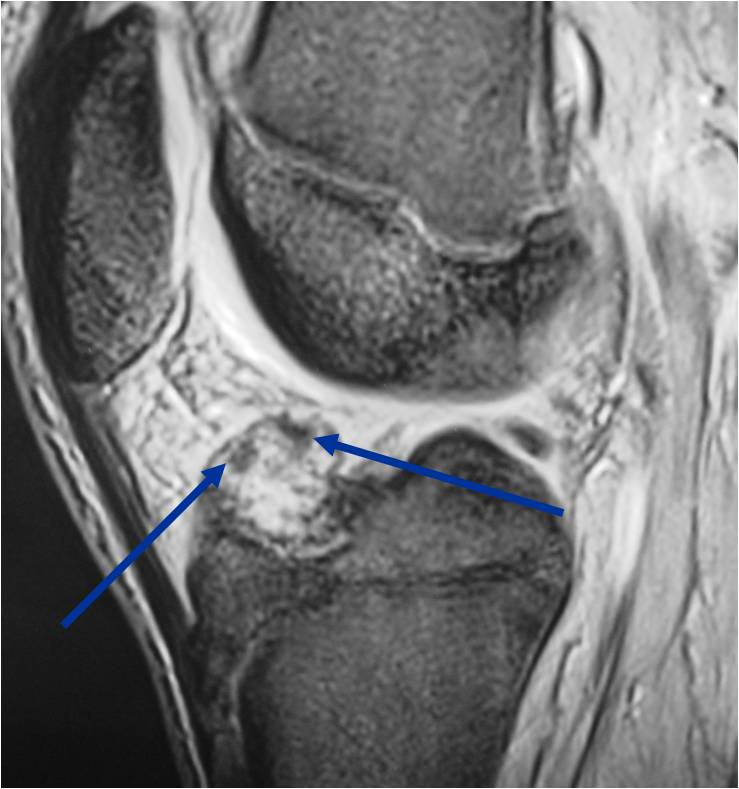

General Information Enchondroma is a benign indolent intramedullary hyaline cartilage neoplasm Accounts for 10% of all benign osseous tumors Limited growth, most lesions are less than 5 cm in maximal dimension Bones grow from a cartilaginous growth plate that...